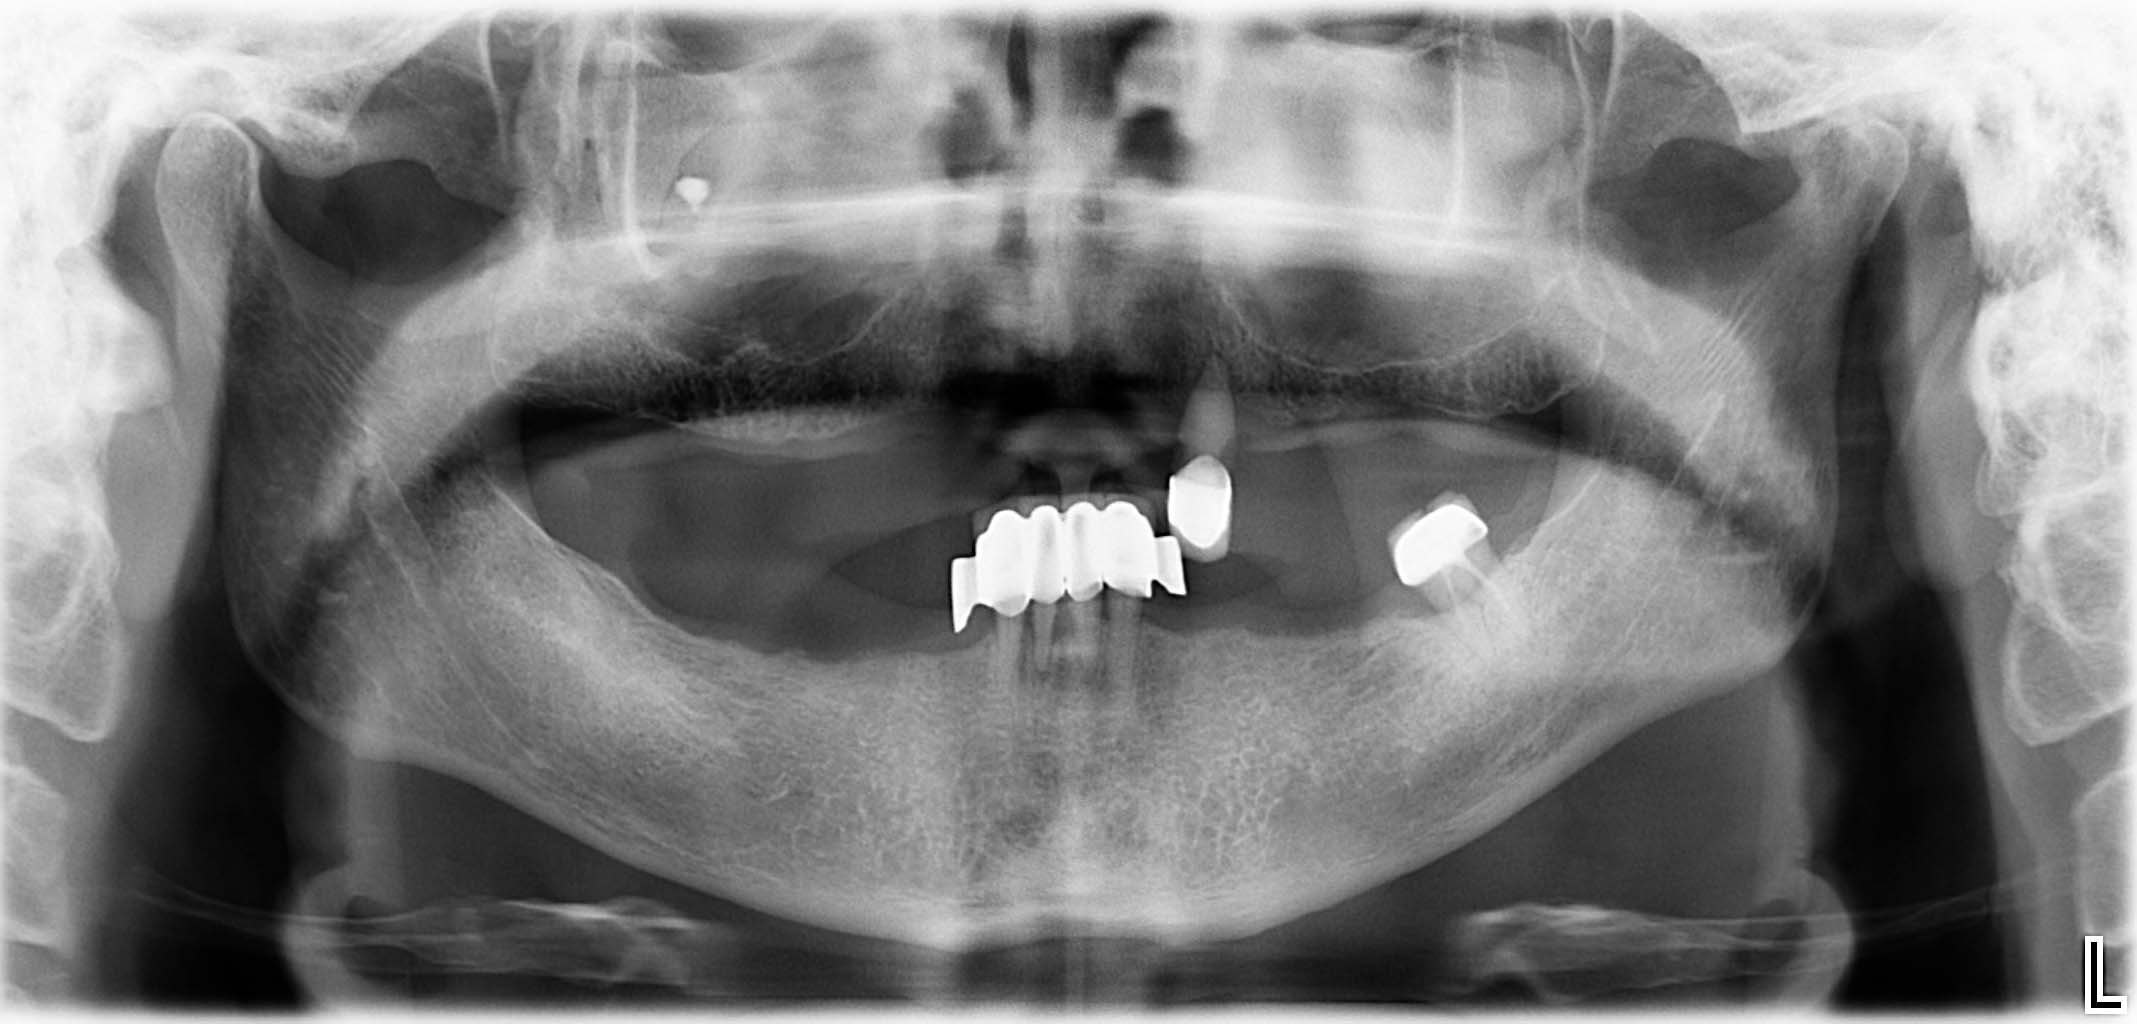

Erfolgreich implantierte Patientenfälle (klinische Fotos)